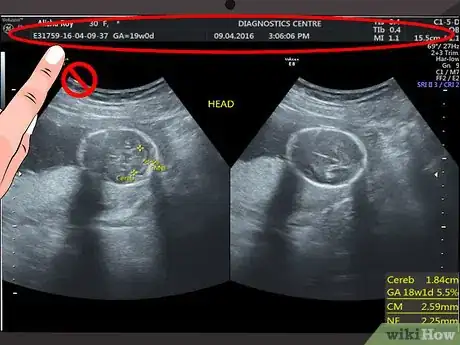

1Disregard the text and numbers at the top of your scan. Most hospitals and ultrasound centers use this space to include details like your name, hospital reference number, or ultrasound machine settings. Since this information does not have anything to do with what you see on the ultrasound image, you can ignore this information.[1]

Measurements will be taken at the time of ultrasound, depending on the gestational age. Early gestations are measured by the crown-rump length, and later gestations are measured by an algorithm using head, abdomen and femur measurements. Determining an accurate gestational age is also dependent on how far along the pregnancy is. If you are dated by measurements that show you to be 6 weeks pregnant, this is extremely accurate. If you are measuring when you are close to your due date, this is extremely inaccurate. -